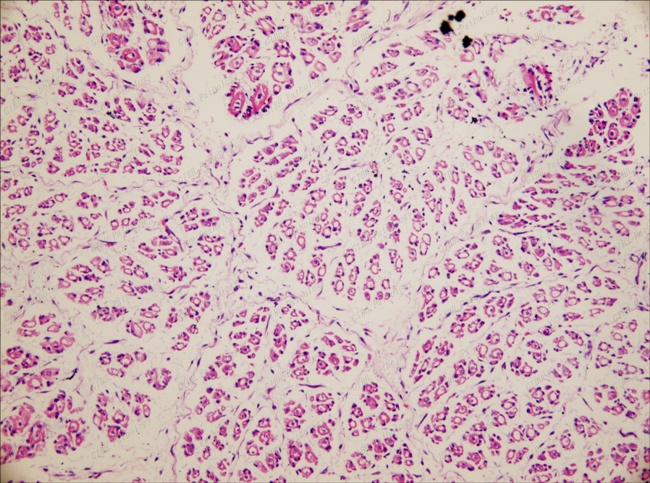

胎豬背肌